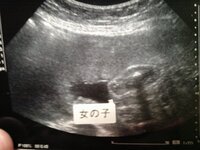

√ 胎児 性別 エコー 女の子 137148-胎児 性別 エコー 女の子

胎児 性別 エコー 女の子